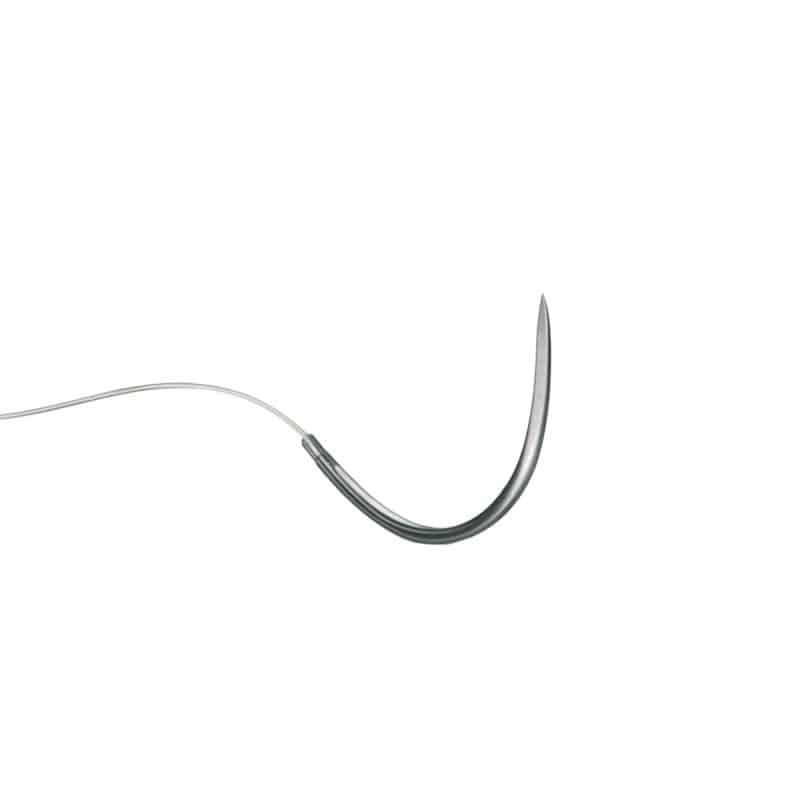

Monosyn® USP4-0 EP1.5 70cm DS12

Monosyn® USP4-0 EP1.5 70cm DS12

The monofilament Monosyn® suture material from B. Braun is medium-term tear-resistant, absorbable and synthetic. The undyed needle-thread combination is individually sterile-packed and available in different thread strengths. The needle is a 3/8 circle with a incisive tip, which is particularly slippery due to its silicone coating and therefore stands out because of its low tissue trauma and exceptional skin penetration properties.

- Needle curvature & point: 3/8 circle with cutting point

- Silicone-coated needles ensure high lubricity

- Low tissue trauma thanks to extraordinary skin penetration properties